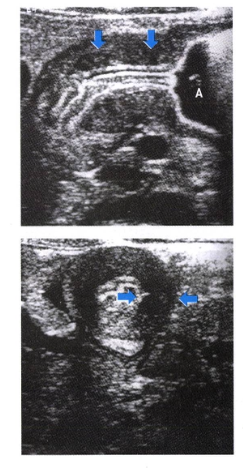

• 초음파 검사: 날문부 근육충 두께 4mm 이상 or 날문부 길이 15mm 이상

• 상부위장관 조영술

• String sign (선상 조영 음영): 좁아진 유문관을 조영제가 가늘게 통과하는 모습

• Shoulder sign (어깨 징후): 비후된 유문 근육이 antrum 쪽으로 돌출된 모습.

• Double track sign (이중 선로 징후): 유문 점막 주름 사이로 조영제가 들어가 두 줄로 보이는 모습